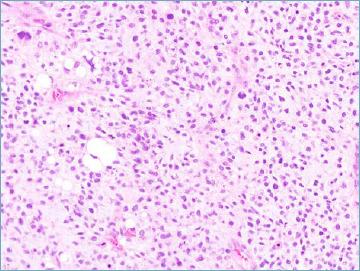

Mesenchymal tumours represent one of the most challenging field of diagnostic pathology and refinement of classification schemes plays a key role in improving the quality of pathologic diagnosis and, as a consequence, of therapeutic options. The recent publication of the new WHO classification of Soft Tissue Tumours and Bone represents a major step toward improved standardization of diagnosis. Importantly, the 2020 WHO classification has been opened to expert clinicians that have further contributed to underline the key value of pathologic diagnosis as a rationale for proper treatment. Several relevant advances have been introduced. In the attempt to improve the prediction of clinical behaviour of solitary fibrous tumour, a risk assessment scheme has been implemented. NTRK-rearranged soft tissue tumours are now listed as an "emerging entity" also in consideration of the recent therapeutic developments in terms of NTRK inhibition. This decision has been source of a passionate debate regarding the definition of "tumour entity" as well as the consequences of a "pathology agnostic" approach to precision oncology. In consideration of their distinct clinicopathologic features, undifferentiated round cell sarcomas are now kept separate from Ewing sarcoma and subclassified, according to the underlying gene rearrangements, into three main subgroups (CIC, BCLR and not ETS fused sarcomas) Importantly, In order to avoid potential confusion, tumour entities such as gastrointestinal stroma tumours are addressed homogenously across the different WHO fascicles. Pathologic diagnosis represents the integration of morphologic, immunohistochemical and molecular characteristics and is a key element of clinical decision making. The WHO classification is as a key instrument to promote multidisciplinarity, stimulating pathologists, geneticists and clinicians to join efforts aimed to translate novel pathologic findings into more effective treatments.